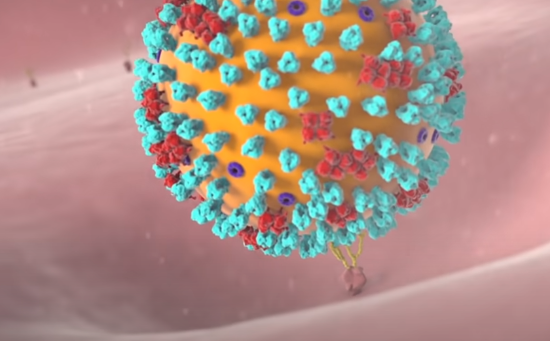

其中,在冠状突起中最重要的一种蛋白叫做刺突糖蛋白(蓝色),这种蛋白可以识别人体细胞的表面ACE2蛋白(黄色)。举个例子,ACE2蛋白像一把锁,一般只有配对的钥匙才能打开它进入细胞内部。一颗合格的病毒会利用自己的技能合成出一把刺突糖蛋白仿制钥匙,堂而皇之的侵入细胞。这个过程就像这样:

如果识别成功,那么接下来在蛋白质外壳的协助下,病毒会使用细胞融合技能进入人体细胞。

整个过程就像病毒利用自己仿制的钥匙开启了人体细胞的大门。